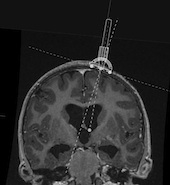

For a controlled placement of the ventricular catheter, the THOMAL GUIDE is placed directly on the skull bone with three feet and with the line markings parallel to the centerline above the drill hole to ensure a right angle of insertion in the sagittal plane. In the coronal plane, an individual angle can be determined using an angle adjustment on the THOMAL GUIDE. The rotation of the catheter guide, which is guided over the rails, is done via a pivot point located very close above the borehole.

A coronary sectional image should be used to facilitate individual measurement of the angle of entry. If possible, this should be at the level of the anterior horn in front of the Foramen Monroi. The entry point, the projected target point and the projected trajectory should be marked on the foramen monroi. To mark the projected target point, the distance to the midline and the depth of the ventricle should be taken into account. Now the tangent can be drawn. The easiest way to do this is to set two points at equal distances medially and laterally from the entry point. The connection of these two points corresponds to the tangent. Accordingly, the angle between the trajectory and the tangent can then be determined and set on the THOMAL GUIDE.